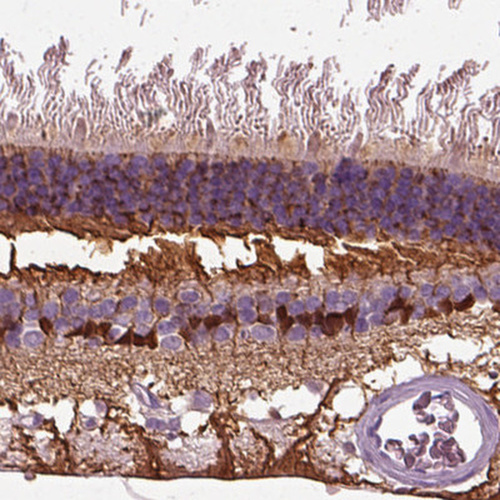

Immunohistochemical staining of human retina shows cytoplasmic positivity in cells in inner nuclear layer and nerve fibers.